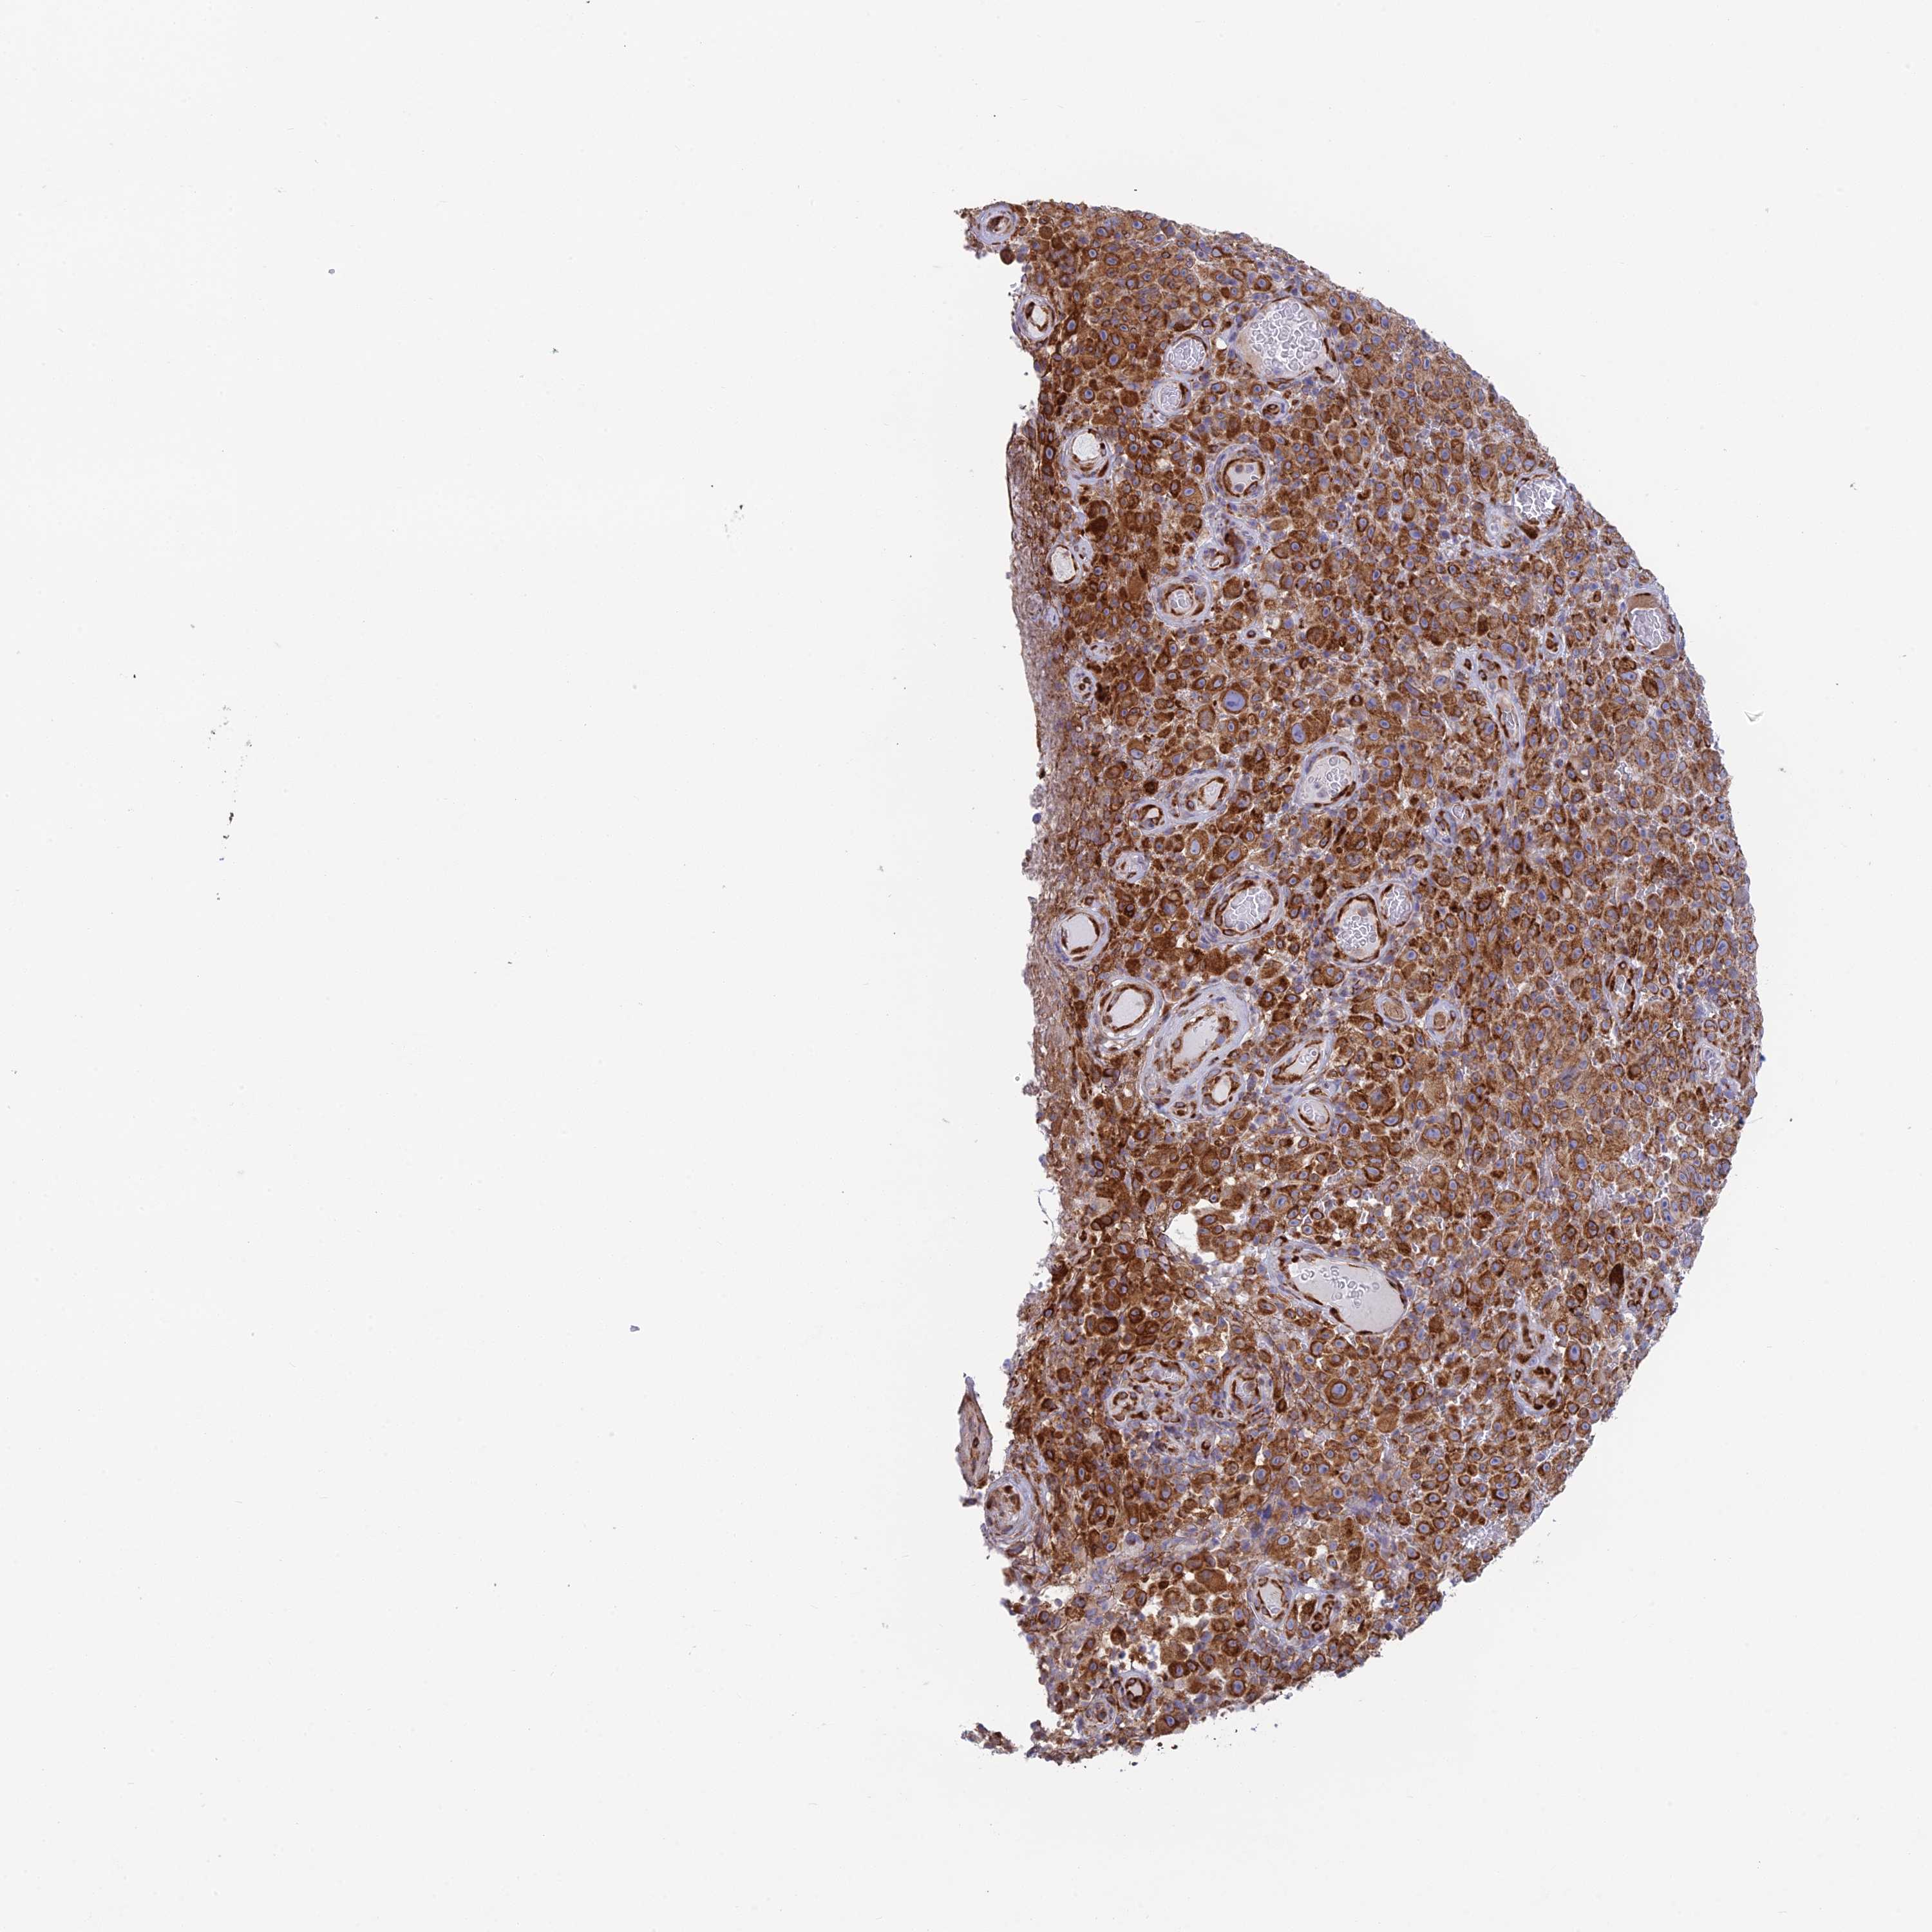

MELANOMA - Protein expressioni

A mouse-over function shows sample information and annotation data. Click on an image to view it in a full screen mode. Samples can be filtered based on level of antibody staining by selecting one or several of the following categories: high, medium, low and not detected. The assay and annotation is described here.

Note that samples used for immunohistochemistry by the Human Protein Atlas do not correspond to samples in the TCGA dataset.

Antibody stainingi

Antibody staining in the annotated cell types in the current human tissue is reported as not detected, low, medium, or high, based on conventional immunohistochemistry profiling in selected tissues. This score is based on the combination of the staining intensity and fraction of stained cells.

Each image is clickable and will lead to virtual microscopy that enables deeper exploration of all samples and also displays staining intensity scores, fraction scores and subcellular localization as well as patient and tissue information for each sample.

Antibody HPA043648

Staining

High

Medium

Low

Not detected

Intensity

Strong

Moderate

Weak

Negative

Quantity

>75%

75%-25%

<25%

None

Location

Nuclear

Cytoplasmic/membranous

Cytoplasmic/membranous,nuclear

Malignant melanoma, NOS

Malignant melanoma, Metastatic site